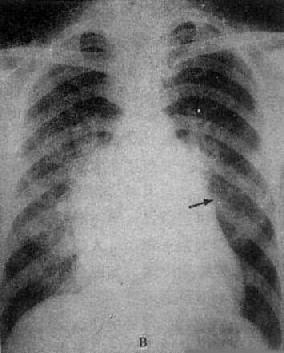

图3-2-16 二尖瓣关闭不全并狭窄

心增大呈二尖瓣型,右心室增大,肺动脉

段突出,左心耳增大,有肺瘀血